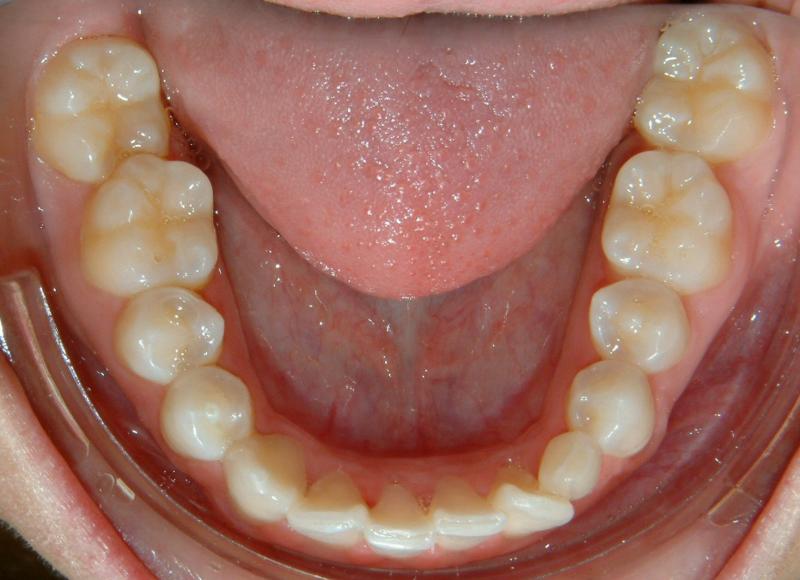

The status of the impacted lower left canine (before orthodontic treatment) are shown in Figs. 13 & 14.

Fig. 15 Initial photograph of impacted lower left canine - unerupted (at 16 y.o., with existing deciduous canine).

© Copyright 2007-2014, Vu Orthodontics. All rights reserved.